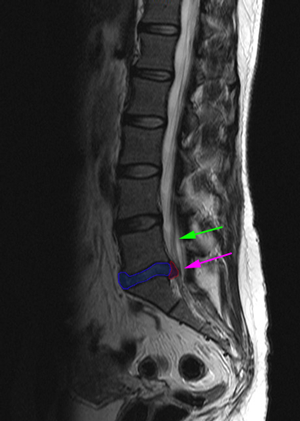

Κήλη οσφυϊκού μεσοσπονδυλίου δίσκου, επίπεδο |